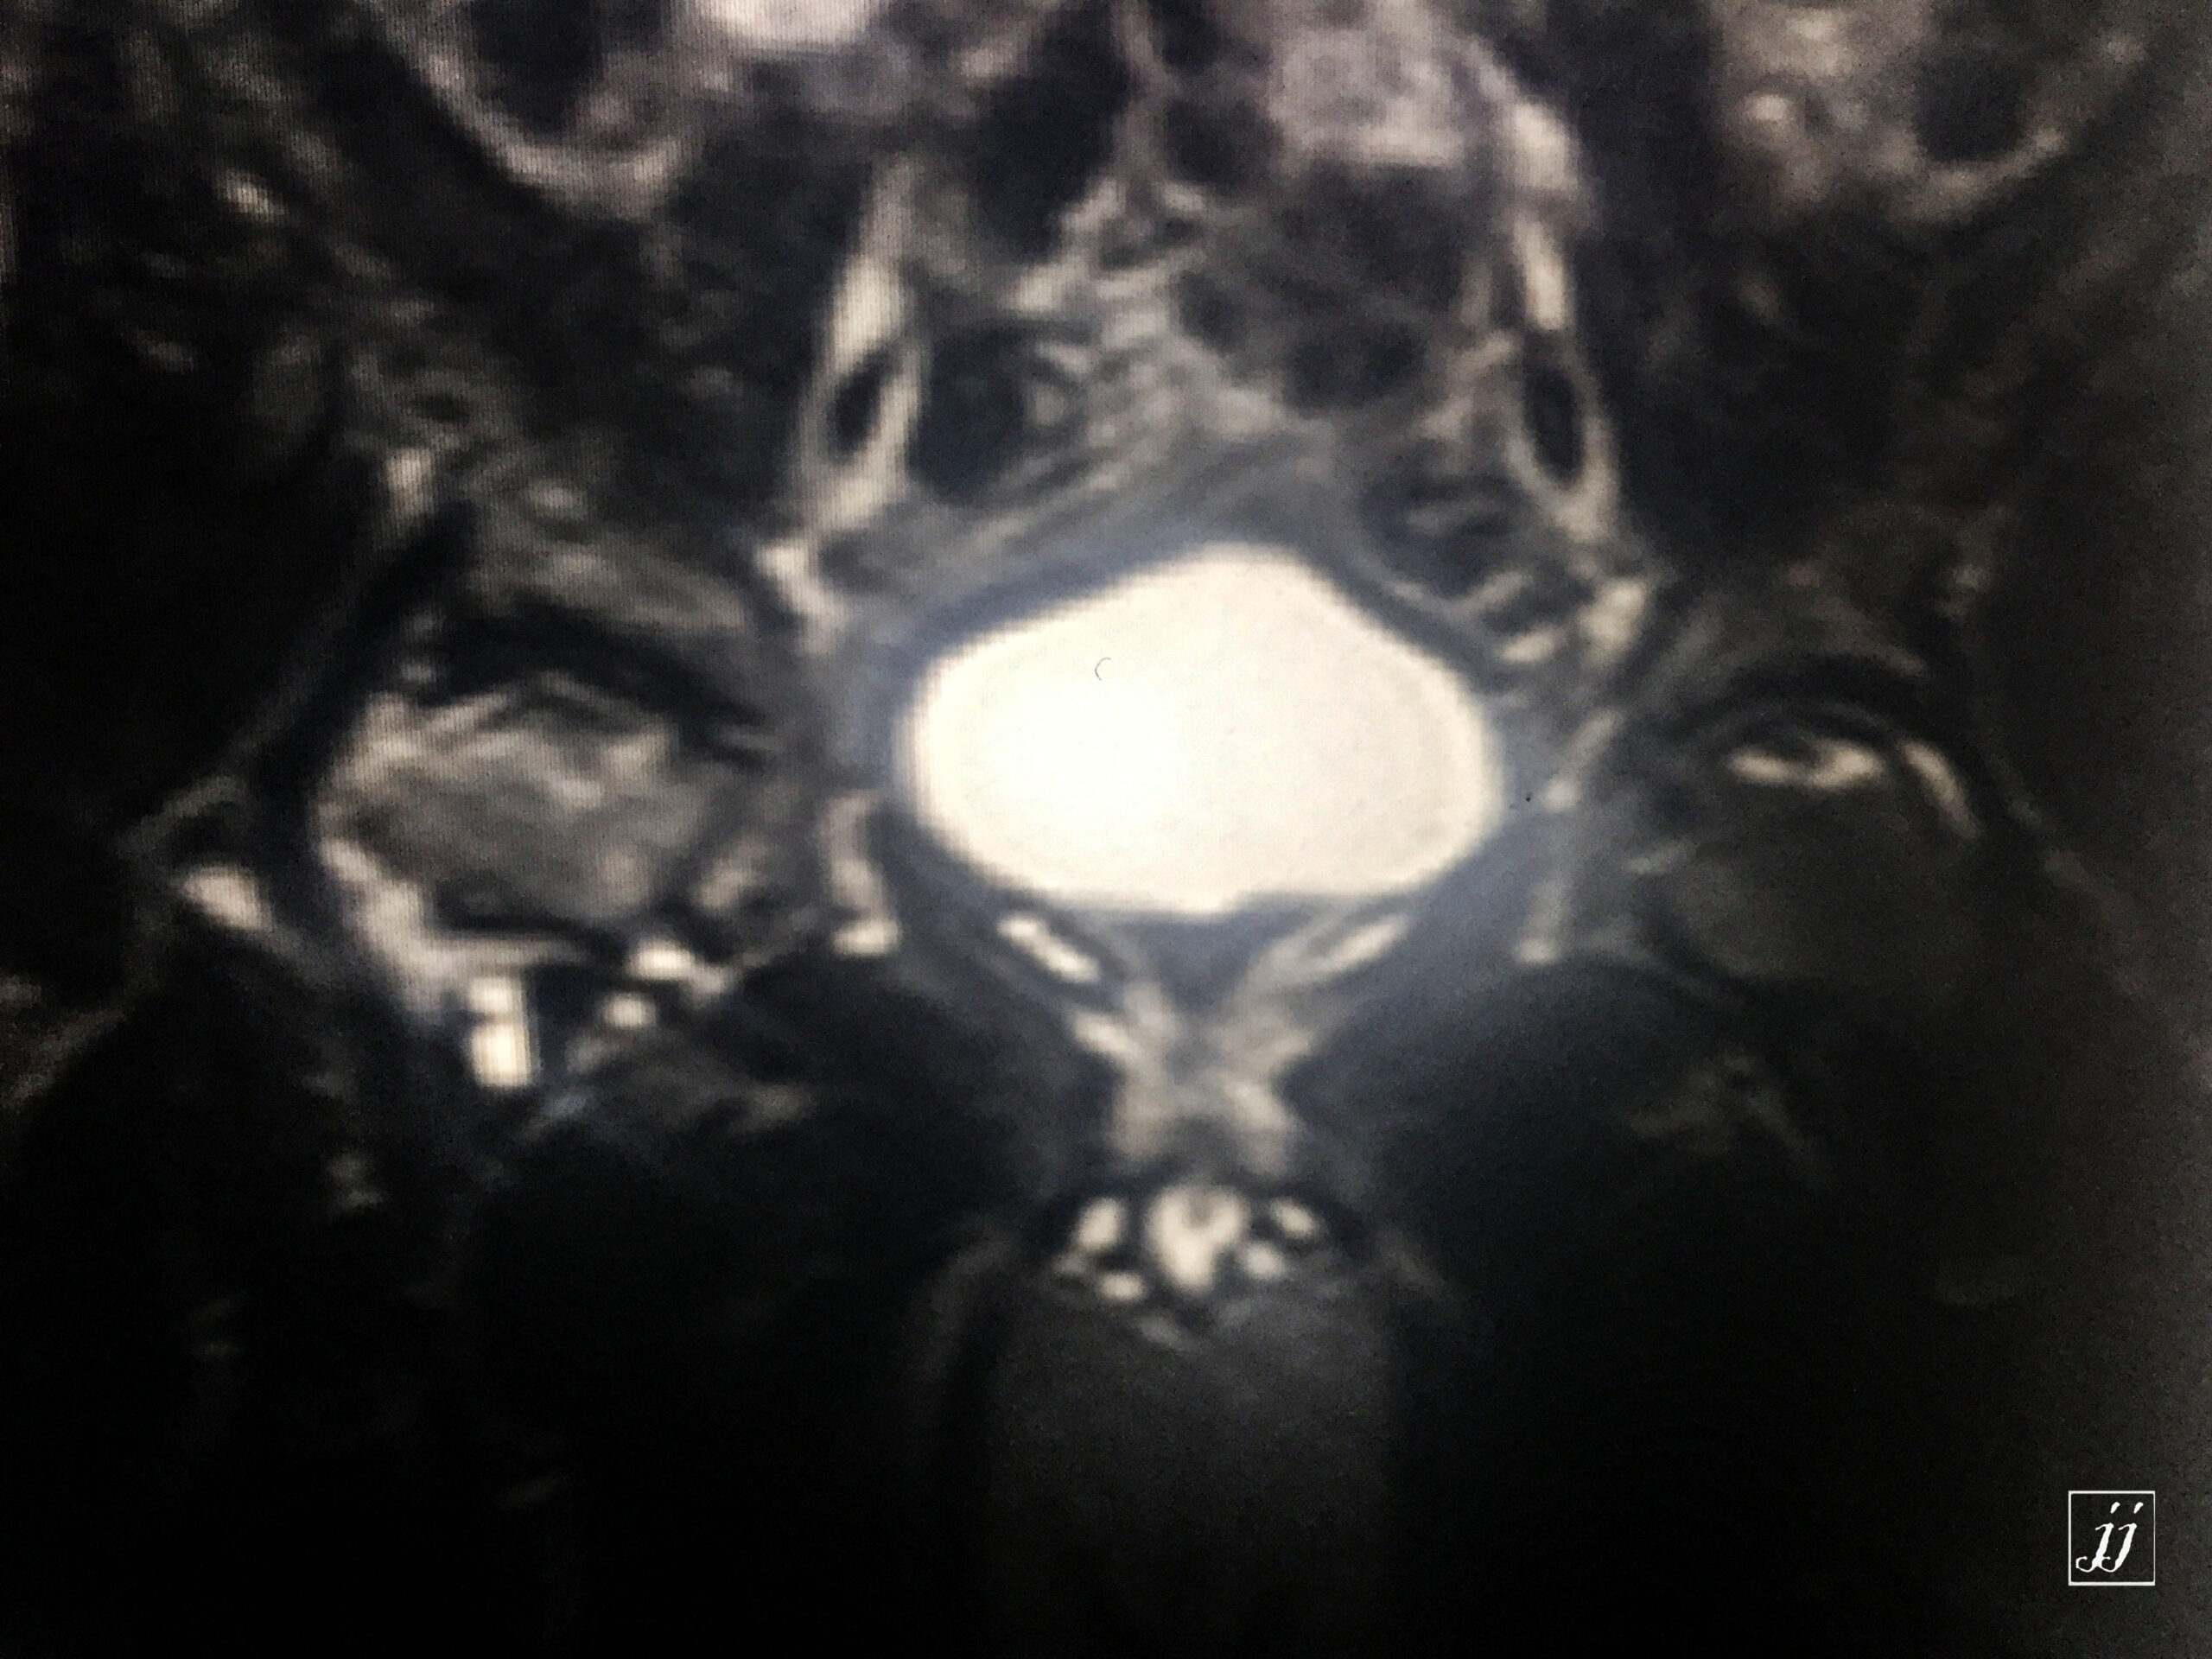

MSK- bi lateral femoral head aVN and right side osteoarthritis (1)